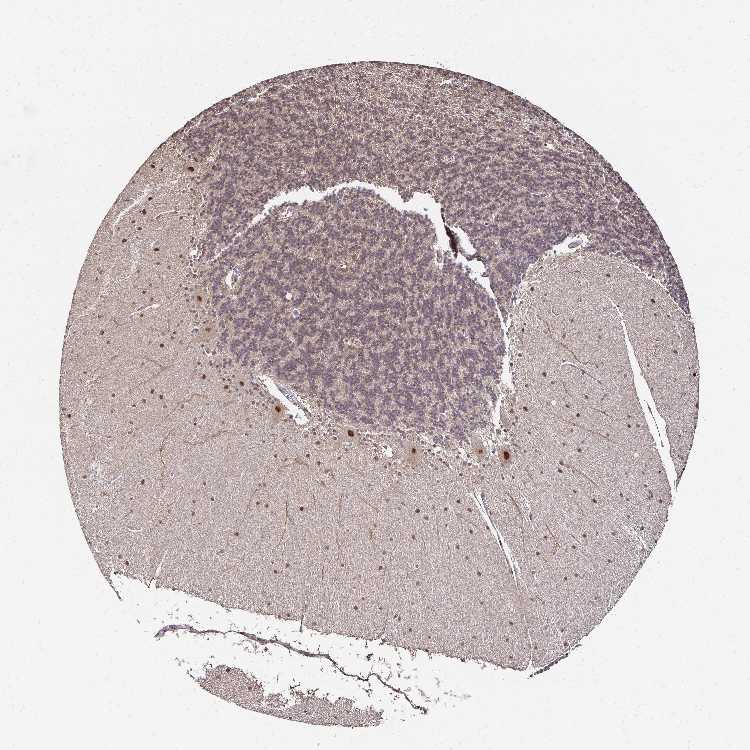

BRAIN CEREBELLUM Show tissue menu

CEREBELLUM - Expression summary

CEREBELLUM - Antibody stainingi

Antibody staining in the annotated cell types in the current human tissue is reported as not detected, low, medium, or high, based on conventional immunohistochemistry profiling in selected tissues. This score is based on the combination of the staining intensity and fraction of stained cells.

Each image is clickable and will lead to virtual microscopy that enables deeper exploration of all samples and also displays staining intensity scores, fraction scores and subcellular localization as well as patient and tissue information for each sample.

Antibody HPA045174Antibody CAB032821

Purkinje cells HighHigh

Cells in granular layer LowNot detected

Cells in molecular layer MediumMedium